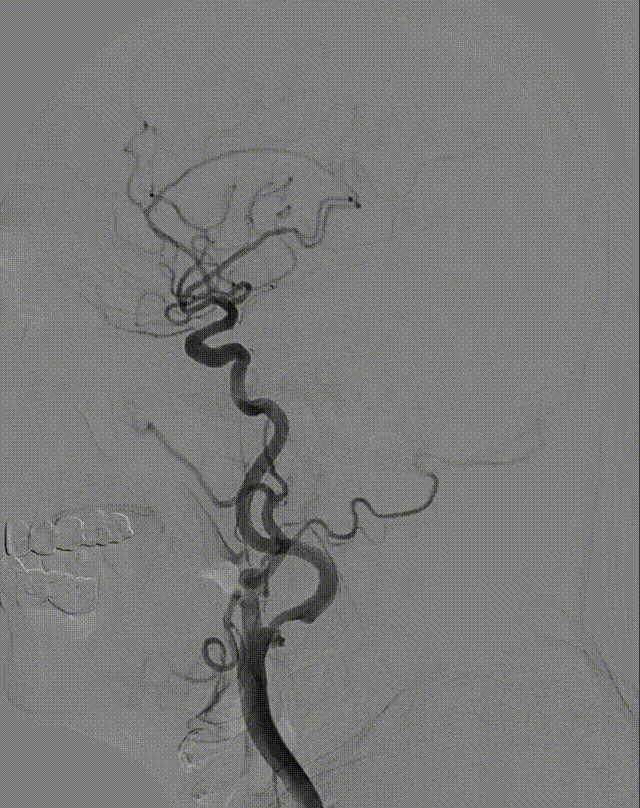

使用雅培Workhorse保护伞导丝先行通过病变狭窄处,随后将Emboshield Nav6保护伞沿导丝推送经过C1端弯曲处。借助Nav6保护伞的支撑,推送6F 115cm中间导管至C1远端,利用特洛伊木马技术将Nav6保护伞输送并放置于颈内动脉C1段。回撤中间导管,在透视状态下释放Nav6保护伞,Nav6圆周骨架在透视下显影清晰,定位准确。

将中间导管撤至颈总动脉,通过Workhorse导丝送入4mm*20mm球囊至右侧颈内动脉狭窄病变处,准确定位后以适当压力预扩狭窄病变,造影示狭窄改善不明显。撤出球囊,再次通过Workhorse导丝送入5mm*30mm球囊至狭窄病变处进行扩张,造影提示狭窄稍改善。

考虑到靶血管较迂曲,拟使用中间导管进行支架释放。在Workhorse导丝引导下,将中间导管通过迂曲段,经由中间导管送入8mm*40mm颈动脉支架至右侧颈内动脉狭窄处。回撤中间导管至颈总动脉后,在透视状态下准确释放支架。

造影显示残余狭窄小于30%,未进行后扩张。术后造影显示狭窄解除,支架置入部位满意,血流较术前明显改善。使用中间导管将Nav6保护伞顺利回收后,对股动脉穿刺点进行止血,患者安返病房。

Nav6由于其出色的安全性和独特的独立导丝技术,已成为CAS手术中术者常规应用的保护伞。在本病例中,由于患者颈内动脉起始处严重狭窄合并S形弯的解剖形态,使得保护伞和支架顺利到位变得挑战。在此类病变中,巧用6F中间导管并借助Nav6输送导管的有效支撑采用特洛伊木马及望远镜技术,可将保护伞顺利输送到C1远端平直处,为后续顺利治疗提供基础。